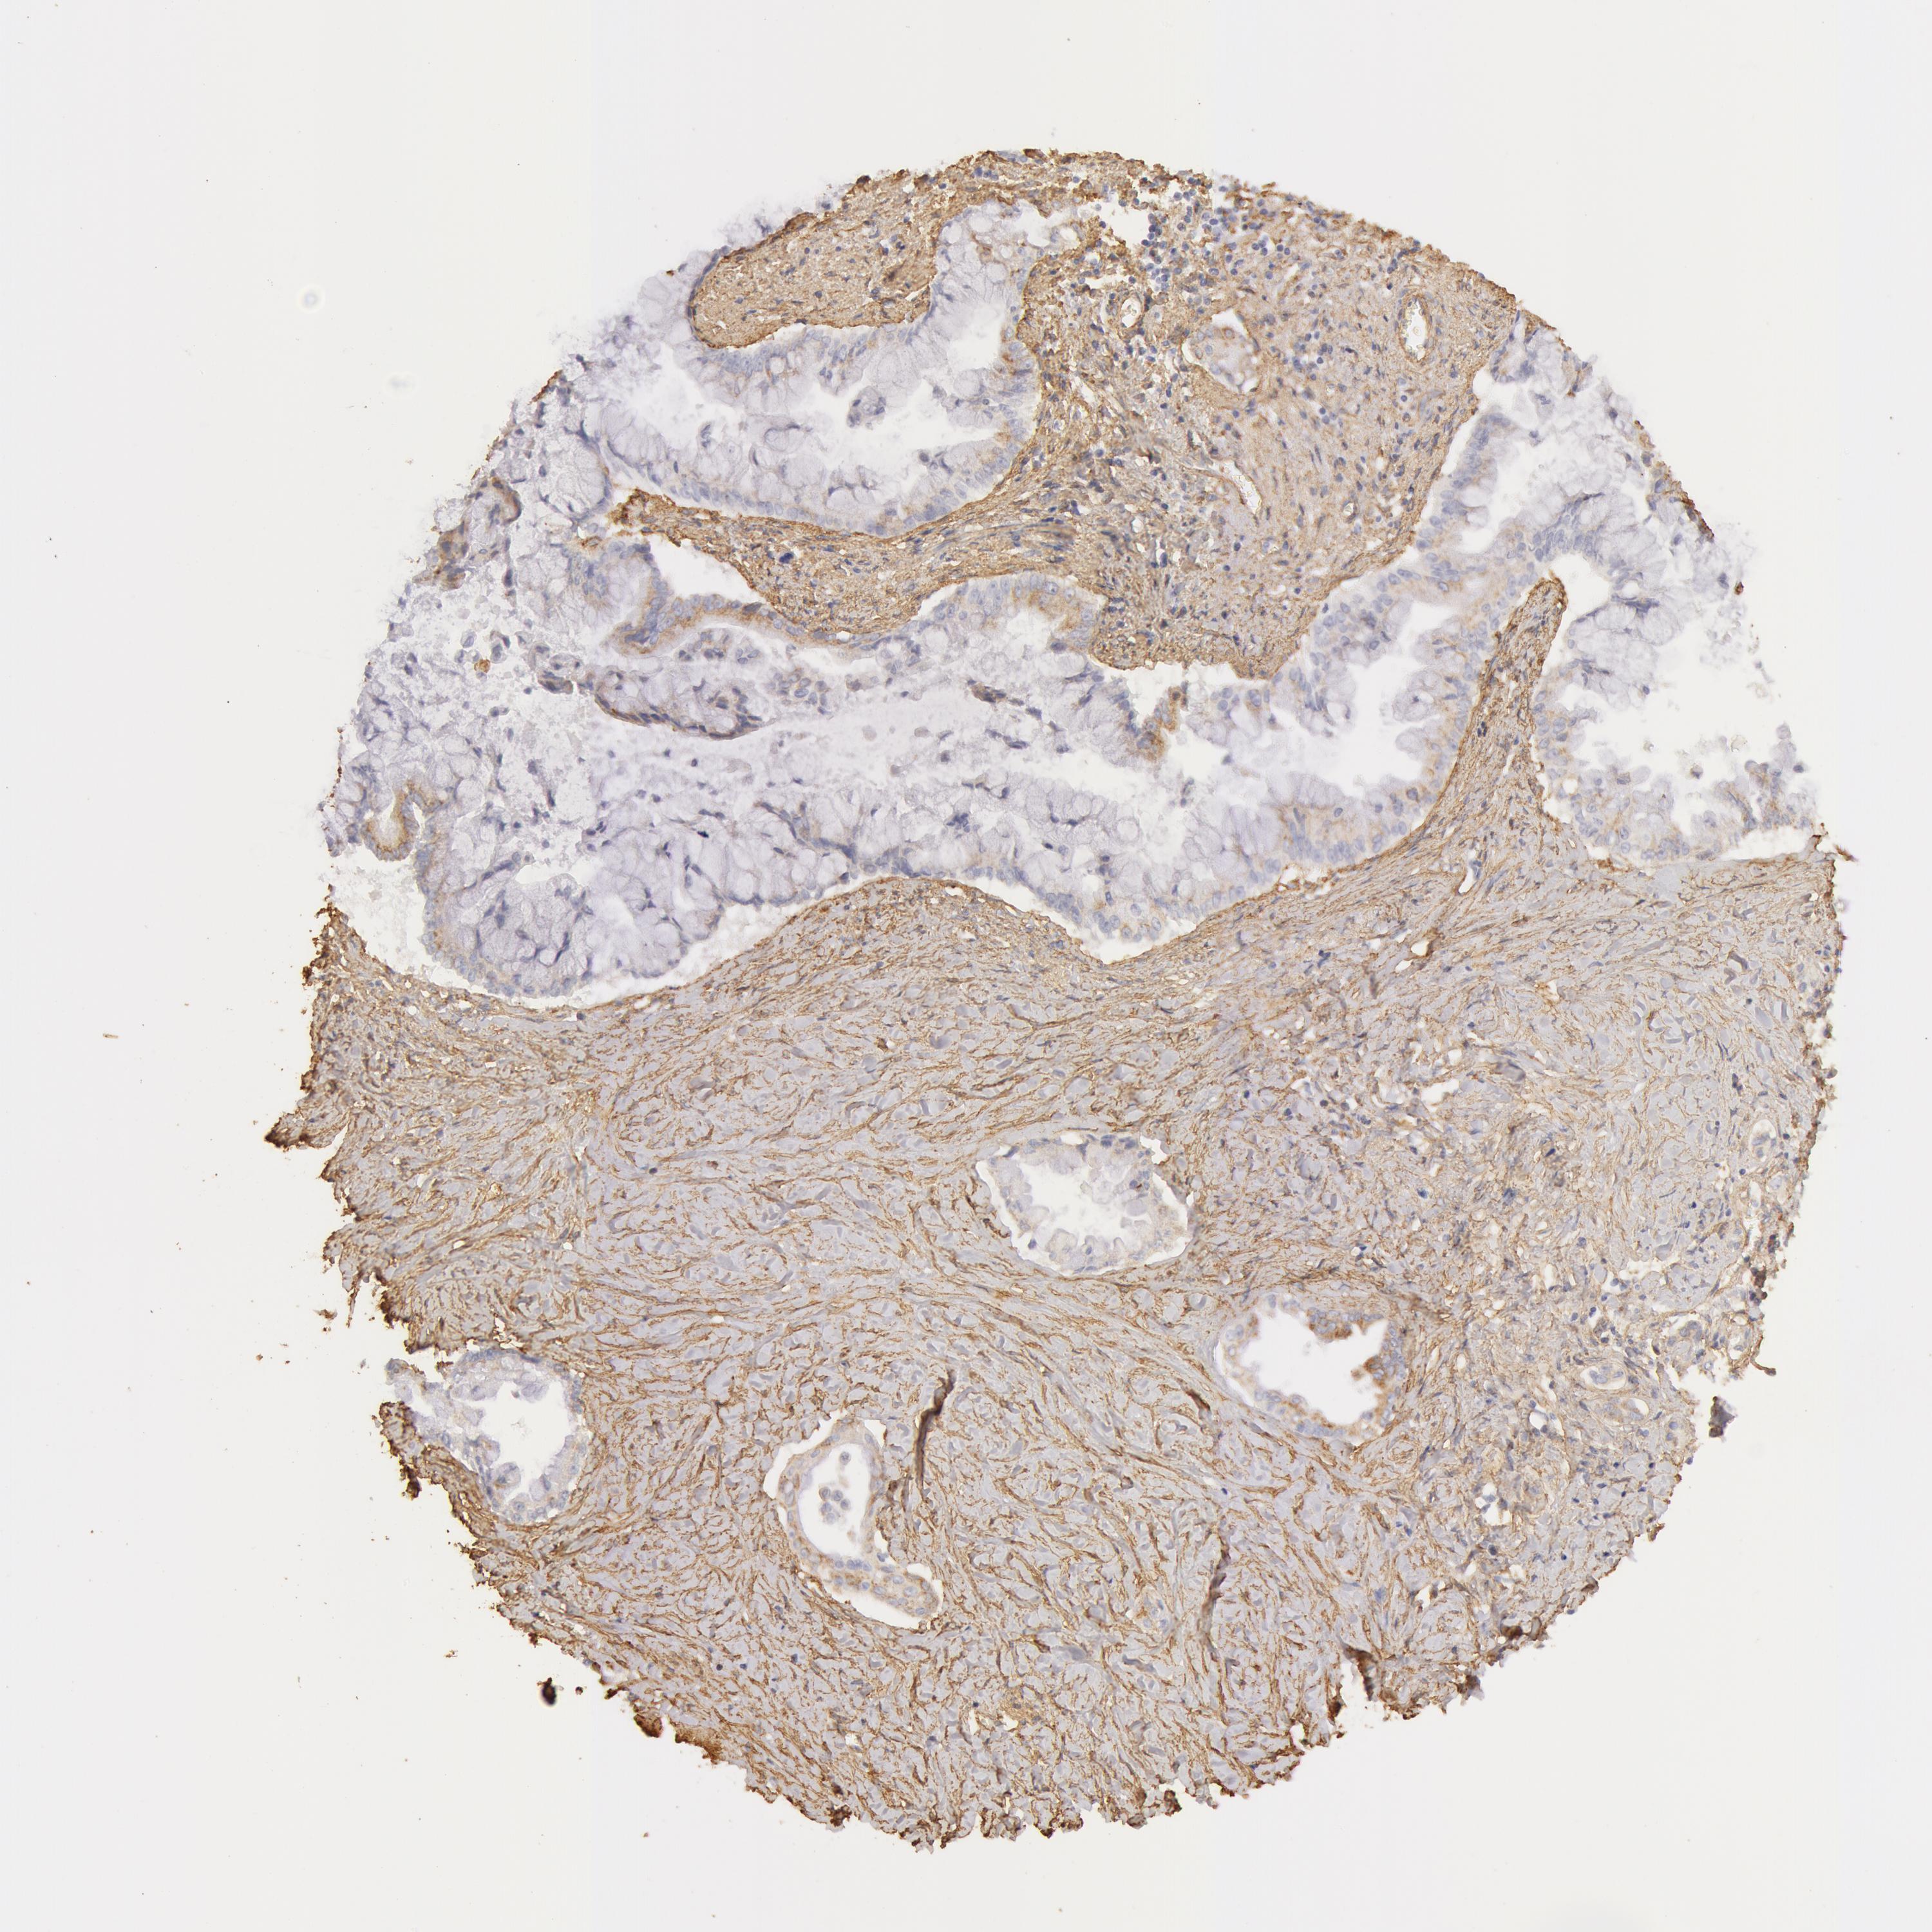

PANCREATIC CANCER - Protein expressioni

A mouse-over function shows sample information and annotation data. Click on an image to view it in a full screen mode. Samples can be filtered based on level of antibody staining by selecting one or several of the following categories: high, medium, low and not detected. The assay and annotation is described here.

Note that samples used for immunohistochemistry by the Human Protein Atlas do not correspond to samples in the TCGA dataset.

Antibody stainingi

Antibody staining in the annotated cell types in the current human tissue is reported as not detected, low, medium, or high, based on conventional immunohistochemistry profiling in selected tissues. This score is based on the combination of the staining intensity and fraction of stained cells.

Each image is clickable and will lead to virtual microscopy that enables deeper exploration of all samples and also displays staining intensity scores, fraction scores and subcellular localization as well as patient and tissue information for each sample.

Antibody CAB001695

Staining

High

Medium

Low

Not detected

Intensity

Strong

Moderate

Weak

Negative

Quantity

>75%

75%-25%

<25%

None

Location

Nuclear

Cytoplasmic/membranous

Cytoplasmic/membranous,nuclear

Adenocarcinoma, NOS